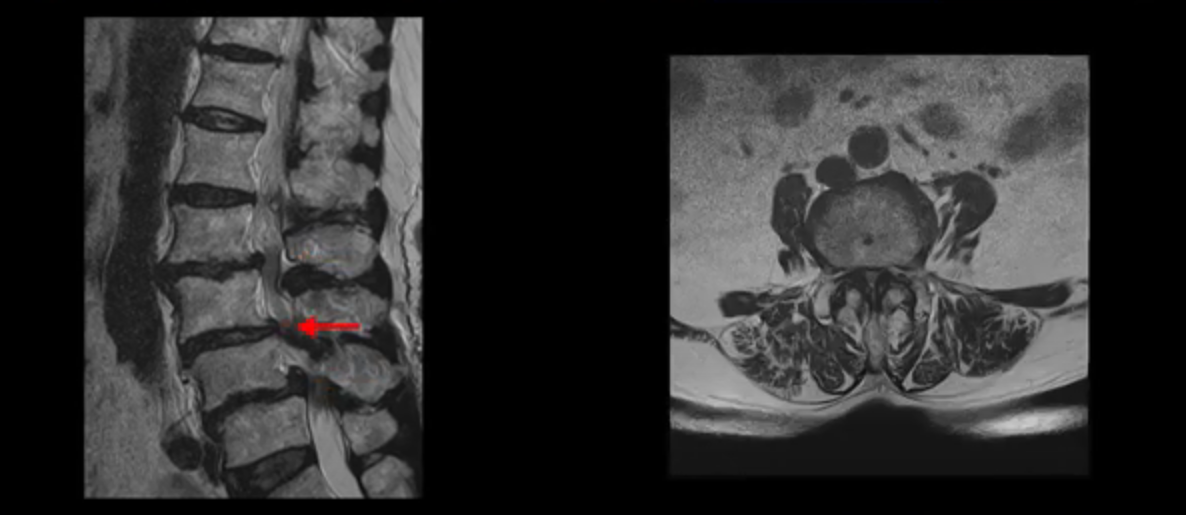

이 환자분 MRI를 보면서 더 자세히 설명 드리겠습니다. 이분은 허리의 다섯 마디가 다 안 좋은 환자분입니다. 84세 고령의 나이에 이렇게 여러 마디가 안 좋으면 대학병원에서도 수술이 어렵다는 얘기를 듣는 경우가 많습니다. 또 수술을 하더라도 결과가 안 좋을 수 있다는 얘기를 들을 가능성이 높습니다.

보시다시피 허리 다섯 마디 전부가 다 퇴행되어 있고,

두 마디에 전방전위증이 있고,

2번 3번,

3번 4번,

4번 5번에 중심성 협착이 심하고

거의 모든 추간공 즉, 신경가지가 좌우로 빠져나가는 구멍이 다 좁아져 있습니다.